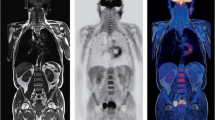

It is common for research brain PET imaging to require dynamic acquisitions for studying tracer kinetics. These are long scans in order to capture both early and late phases of the tracer uptake. In these cases simultaneous PET/MR acquisition is prefered, from the workflow perspective, as MR scans can be acquired at the same time. One example is given in Fig. 3.1 for an application in neuro-oncology [22].

Example protocol for PET/MR scan in neuro-oncology, comprising a dynamic 18F-FET PET and several MR acquisitions, where CSI Chemical Shift Imaging, UTE Ultra-Short Time Echo, ce contrast enhanced scan (Adapted from Neuner et al. [22])

In clinical practice, shorter, static scans are more common. The most predominant brain PET indications include assessment of dementia with FDG or Amyloid imaging, surgical planning for focal epilepsy with FDG and to a lesser extent Parkinson’s disease with 18F-DOPA. Neuro-oncology uses tracers for metabolic assessment, receptor imaging and hypoxia as, and in addition to the list in Table 3.1. Most of these scans are static and, although shorter than many dynamic acquisitions, are still longer than the individual bed-position duration in whole-body protocols, requiring still 15-20 min as a crude average. In these cases, diagnostic MR may require longer acquisitions, again due to several different contrasts that may be required. Two generic imaging protocols for such scans are illustrated in Fig. 3.2 for simultaneous and sequential acquisitions. In both cases, the MR scans can start before or after PET depending on the workflow of the department and, in some occasions, MR scans may start during the radiotracer’s uptake time [59].